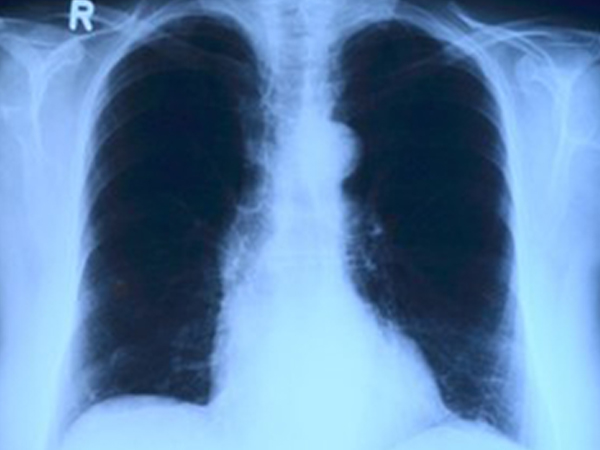

- Chest x-ray or CT scan: The test is used to check the lungs for scars [11] .